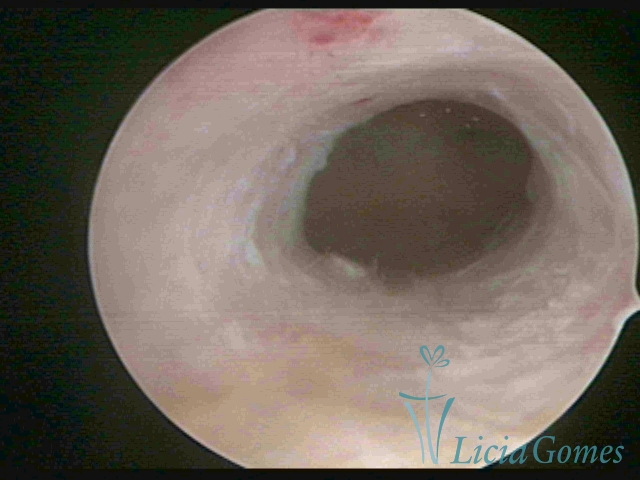

Segunda porção ou setor médio

No terço ou setor médio do canal cervical perdemos o detalhe das papilas, sendo possível a visualização de pregas e criptas. Normalmente observamos os sulcos longitudinais, que são os tecidos mais compactos, com a superfície mais vascularizada, cujos vasos seguem o seu trajeto.